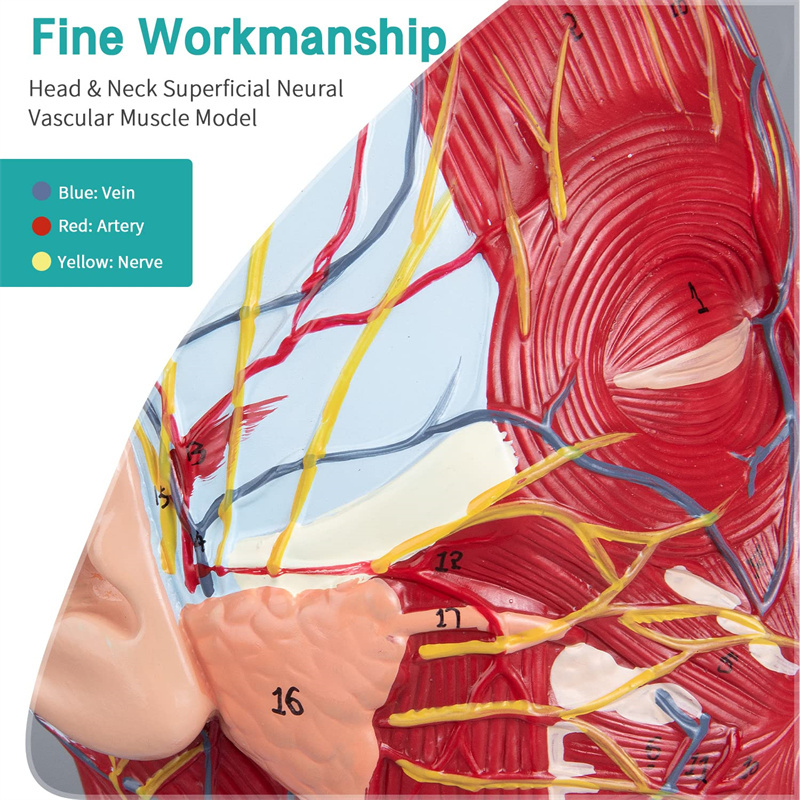

【1: 1 לייווז】 מידיאַן אָפּטיילונג פון 1: 1 נאַטירלעך גרויס קאָפּ & האַלדז אויבנאויפיקער נעוראַל וואַסקיאַלער מוסקל מאָדעל (רעכט זייַט). פייַן ווערקמאַנשיפּ. פאָרשלאָגן אַ פול קייט פון אַנאַטאַמיקאַל פֿעיִקייטן.

【הויך קוואַליטעט】 מאַרך אַנאַטאָמי מאָדעל, געמאכט פון ניט-טאַקסיק ינווייראַנמענאַלי פרייַנדלעך פּווק מאַטעריאַל, גרינג צו ריין. אַנאַטאָמי מאָדעלס זענען האַנט-פּיינטיד און פארזאמלט מיט די מאַקסימאַל ופמערקזאַמקייט צו דעטאַל.

【Superficial Neurovascular Muscle Model】Highly detailed, numbers marked, detachable ear, deepen the understanding of the superficial muscles, vessels, nerves and the internal structures of the head & neck. רויט-אַרטעריע, בלוי-אָדער, געל-נערוו.

【פֿעיִקייטן】 עס געוויזן די אויבנאויפיקער מאַסאַלז פון די יקספּאָוזד פּנים; די אויבנאויפיקער בלוט כלים & נערוועס פון די פּנים & סקאַלפּ; די ינער סטראַקטשערז פון פּאַראָטיד דריז & אויבערשטער רעספּעראַטאָרי שעטעך; די סאַגיטטאַל קרייַז-אָפּטיילונג סטרוקטור פון די סערוואַקאַל רוקנביין.

דער מאָדעל ווייַזן דעטאַילס פון די רעכט קאָפּ האַלדז און מיטן סאַגיטטאַל אָפּטיילונג פון דער מענטש. אַרייַנגערעכנט די אויבנאויפיקער

מאַסאַלז פון די יקספּאָוזד פּנים; די אויבנאויפיקער בלוט כלים און נערוועס פון די פּנים און סקאַלפּ; די ינער סטראַקטשערז

פון פּאַראָטיל דריז און אויבערשטער רעספּעראַטאָרי שעטעך; די סאַגיטטאַל קרייַז-אָפּטיילונג סטרוקטור פון די סערוואַקאַל רוקנביין.

דער מאָדעל געוויזן די היגע מאָרפאַלאַדזשי פון די מעדיאַל און לאַטעראַל סאַגיטטאַל סעקשאַנז פון די קאָפּ און האַלדז און די וואַסקיאַלער און נערוו סטראַקטשערז, מיט אַ גאַנץ פון 100 פּלאַץ ינדאַקייטערז.

דער מאָדעל איז נאַטירלעך גרויס קאָפּ און האַלדז אויבנאויפיקער נעוראָוואַסקולאַר מוסקל מאָדעל, 1 קאָמפּאָנענט, ווייַזונג די דעטאַילס פון די מענטשלעך רעכט קאָפּ און מעדיאַן סאַגיטטאַלע אָפּטיילונג, אַרייַנגערעכנט די יקספּאָוזד בעשאָלעם און די מעדיאַל סטרוקטור פון די פּאַראָטיד דריז און אויבערשטער רעספּעראַטאָרי שעטעך, און די סאַגיטטאַל אָפּטיילונג סטרוקטור פון די סערוואַקאַל רוקנביין